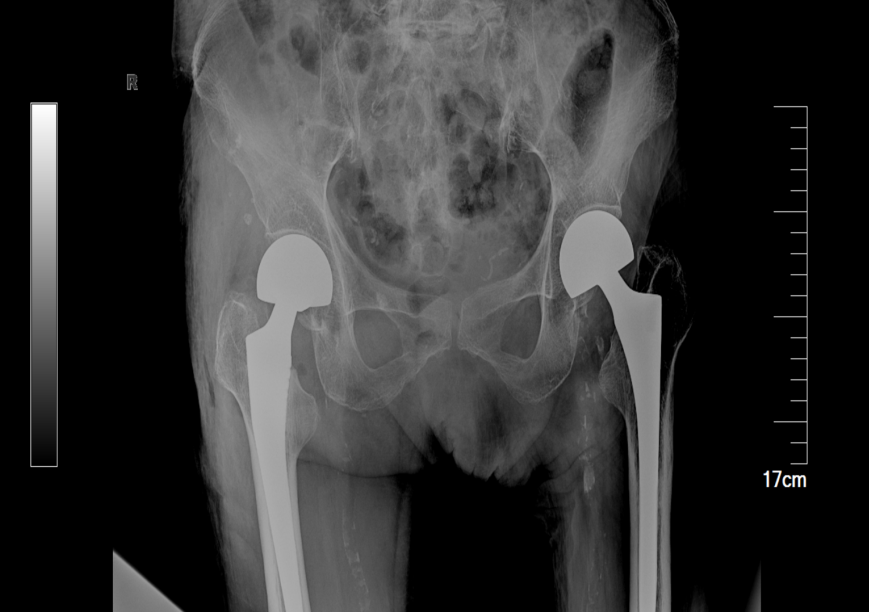

入院后,检查结果显示患者存在多项危急指标:心肌标志物异常、凝血功能紊乱,同时伴有感染迹象。关节·创伤外科徐永申主任立即启动髋部骨折多学科诊疗(MDT)机制,联合手术部、心内科、呼吸科、营养科专家进行紧急评估。经讨论,团队决定先稳定患者全身状况,控制感染、调节心肺功能,在患者内环境改善后,再为其实施「人工股骨头置换术」。该手术具有时间短、创伤小的特点,更适合高龄患者,有助于术后快速康复。

经过充分的术前准备,手术如期进行。在手术部麻醉医师的有力保障下,手术过程顺利,术后患者生命体征平稳。此后,老人虽一度出现术后谵妄,但在关节·创伤外科与手术部的共同干预下,症状于术后第三日得到有效控制,老人的神志也逐渐清醒。